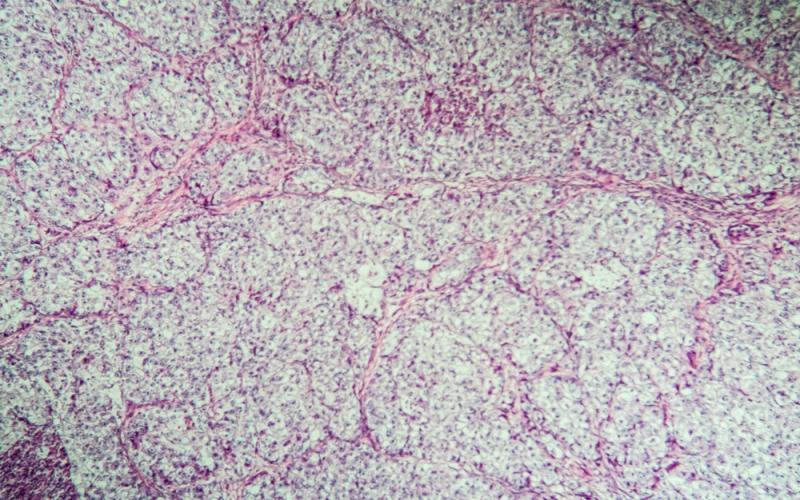

There are 3 types of ovarian cancer—epithelial, germ cell, and stromal cell cancers. Epithelial accounts for more than 80% of the cases and forms in cells on the outer surface of the ovary. Germ cell cancers are caused by abnormal growth of the cells that form eggs. Stromal cell cancers are very rare and typically do not spread beyond the ovaries.7

HE4 is expressed in the glandular epithelium of the reproductive tract, distal renal tubules and respiratory epithelium, however the highest serum levels of HE4 are found in epithelial and serous ovarian cancer and also endometrioid cancer.